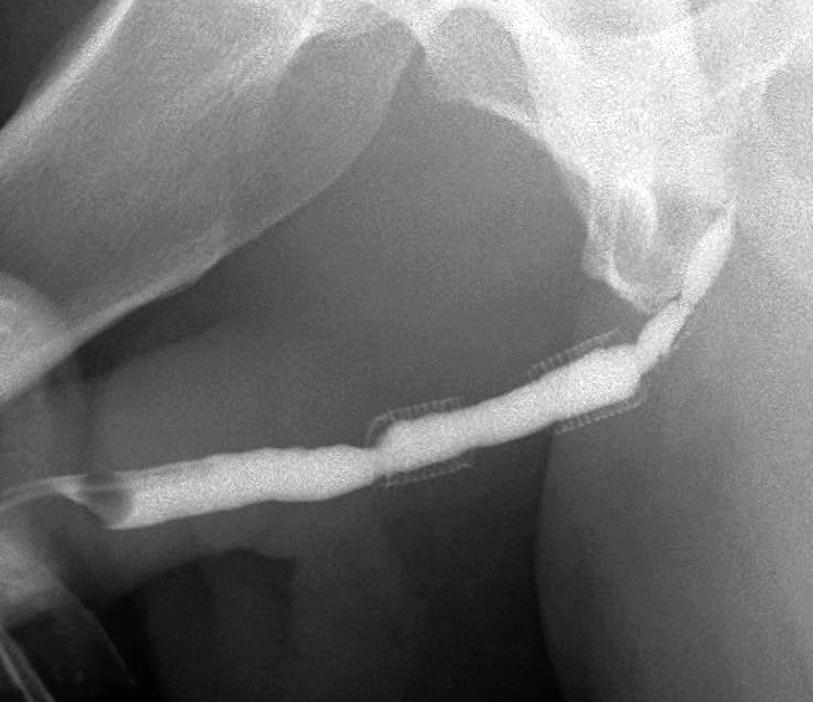

Two 2.0 cm UroLume stents placed on pendulous and bulbar urethra with re-stricture adjacent to both proximal and distal ends of the tandem stented segment